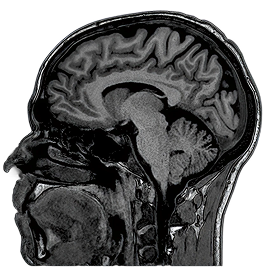

3D T1

1.5T

3D MPRAGE

1.0 x 1.0 x 1.0mm

5:45

0.5T

3D SPGR

1.1 x 1.1 x 1.1mm

5:30